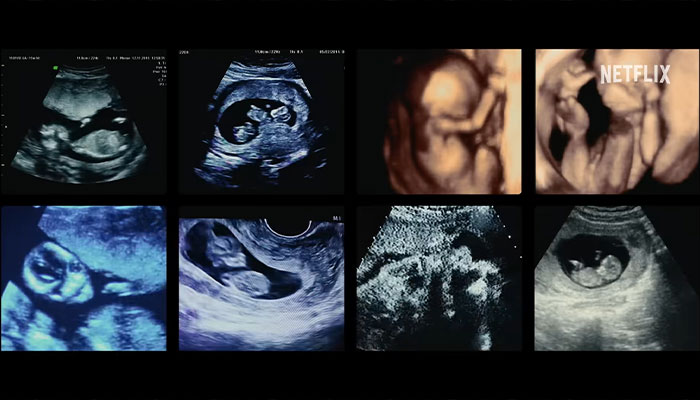

Premiering on July 3, 2024, the three-episode documentary explores Meijer’s claim to have fathered hundreds, if not thousands, of children through sperm banks worldwide.

The feature highlights allegations that Meijer misled families about the extent of his donations, leading to concerns about accidental incest and ethical breaches within the fertility industry.

Image credits: Netflix